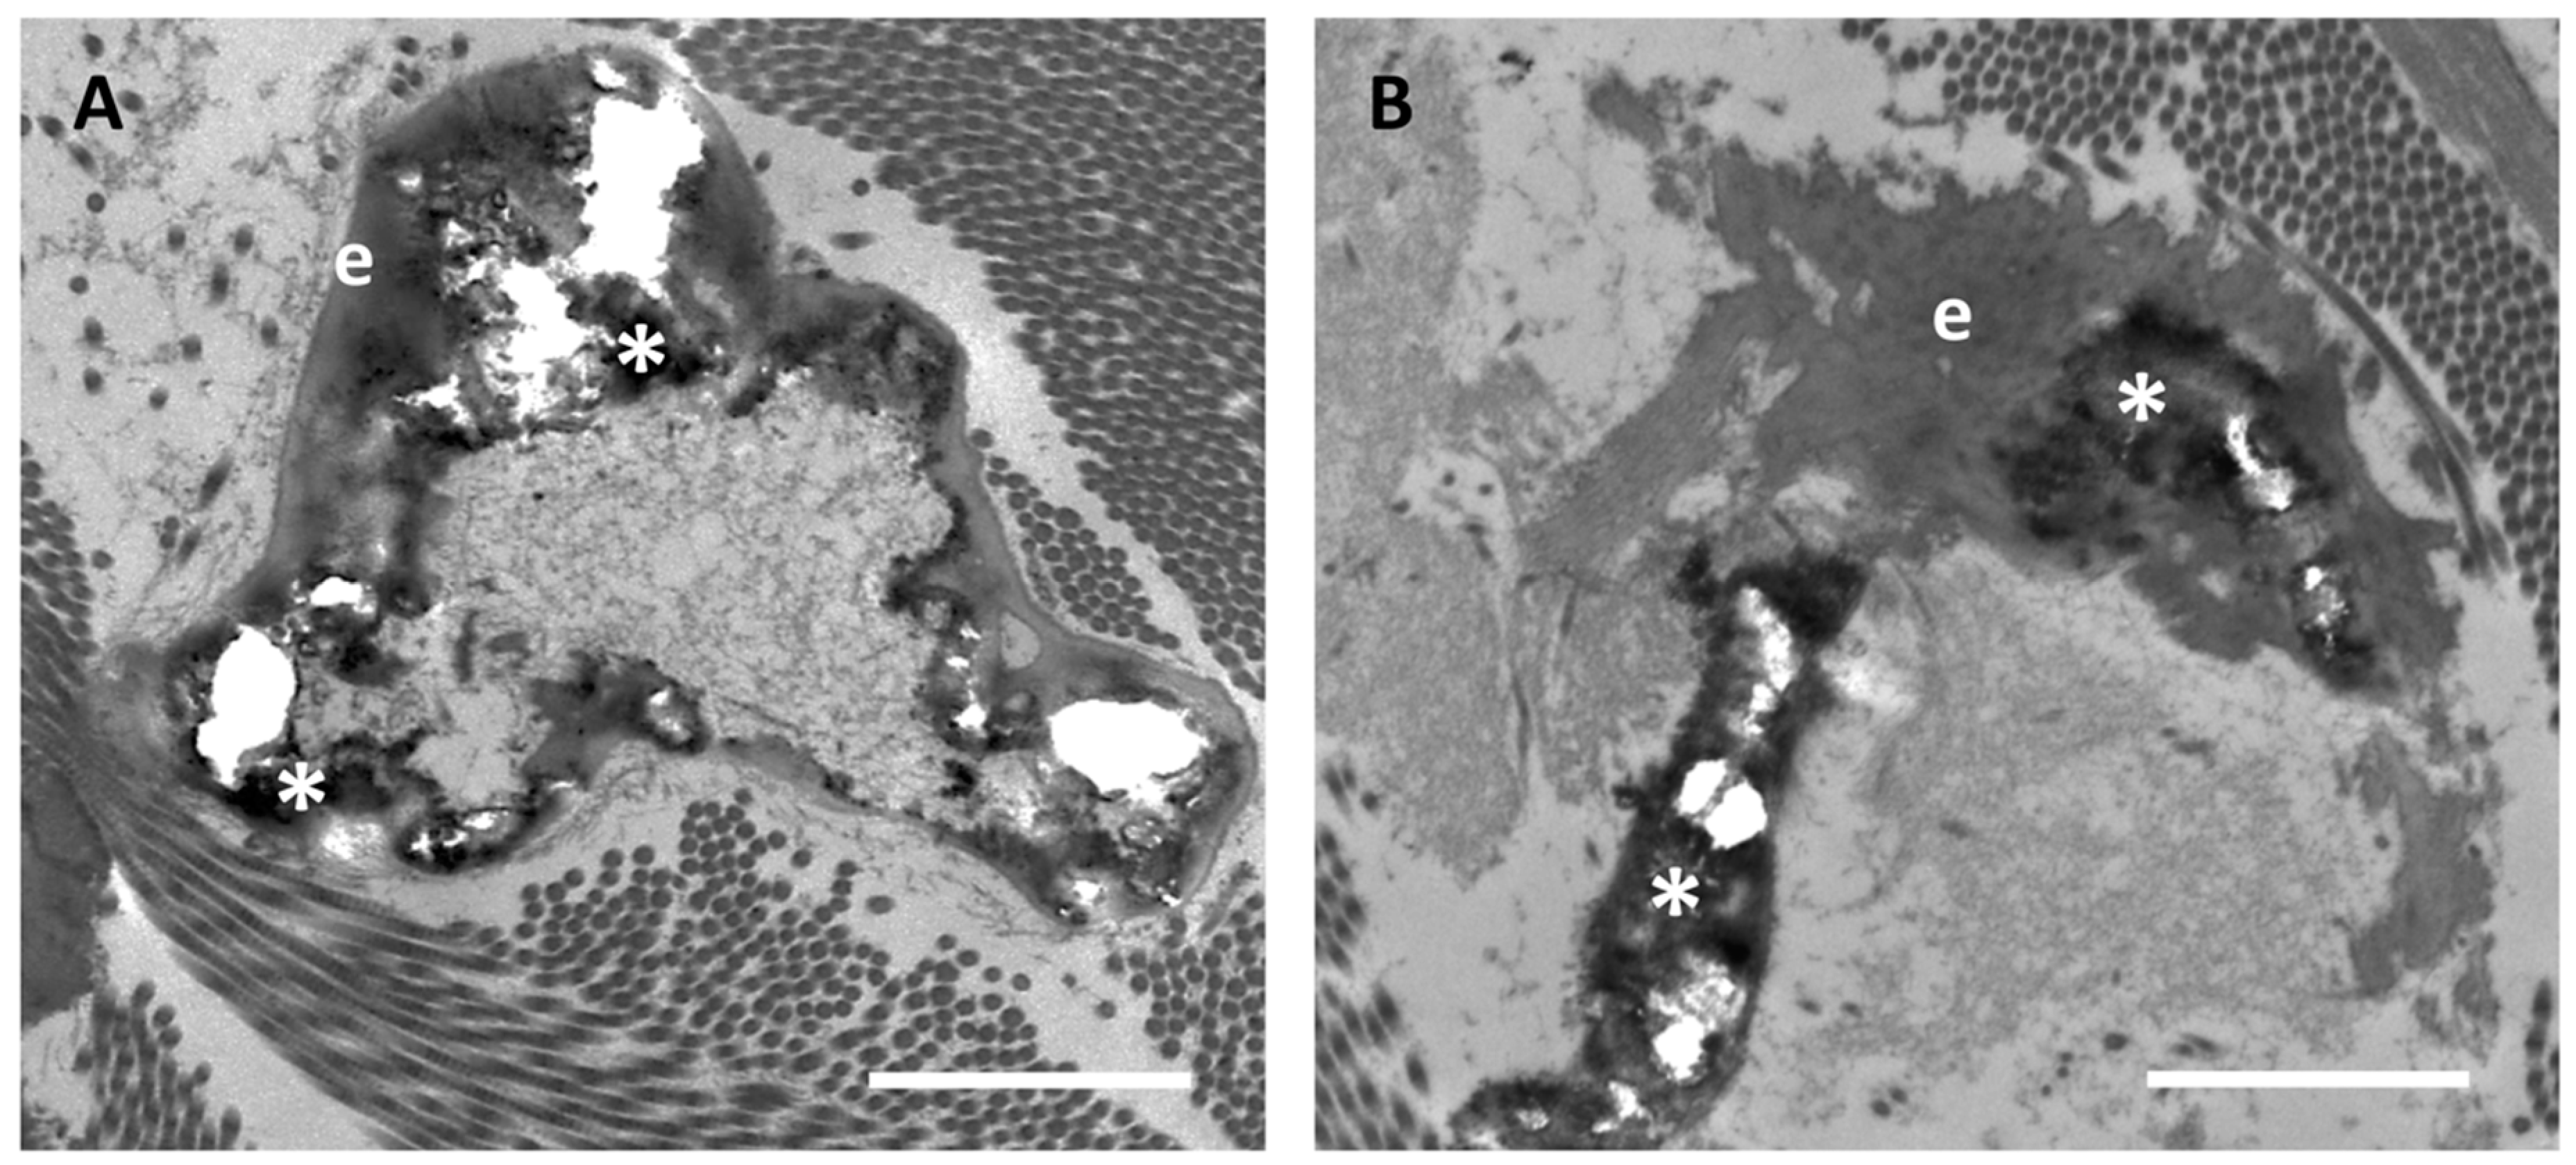

3.1. Calcified and/or Degraded Elastic Fibres in Clinically Unaffected Skin